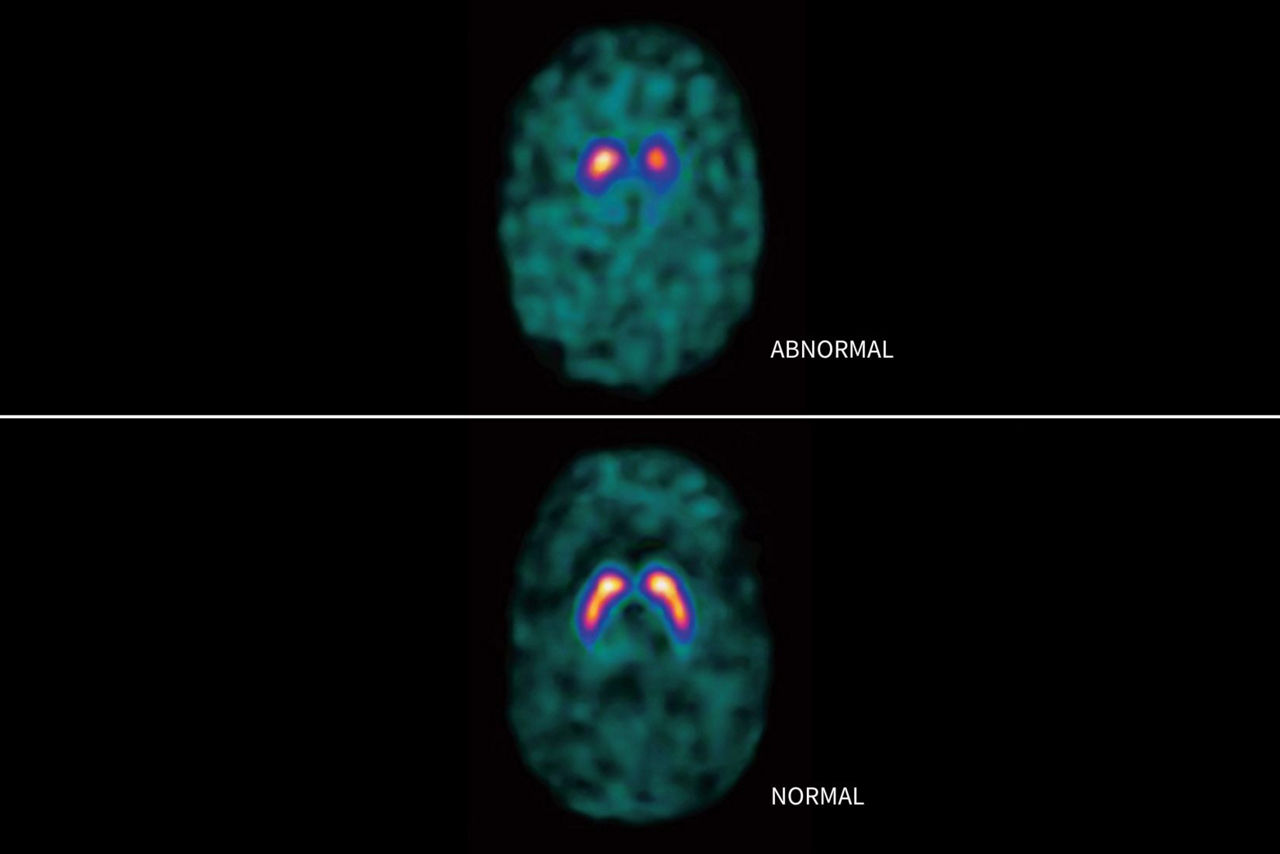

DaTSCAN ist bestimmt zur Ermittlung des Verlusts funktionsfähiger dopaminerger Neuronenendigungen im Striatum.

DIAGNOSTISCHE KLARHEIT

Diagnose durch Dopamintransporter-Bildgebung (DaT-Bildgebung)